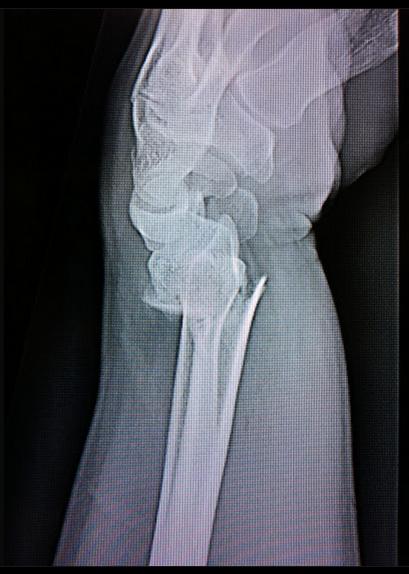

One thing we did find was some soft boggy water, my mate decided he would venture and check it out in his Land Rover, well lets say I noticed him sitting on a weird angle and I proceeded to drive down to help him. He was bogged and not going anywhere.... WELL I got out and started running the winch rope out to him, he got out of his fourby and decided to help, this resulted in him slipping in the wet slippery mud and sustaining a distal fracture to his left radial bone. Well we splinted it up and drove him to the hospital..

And the resulting injury...